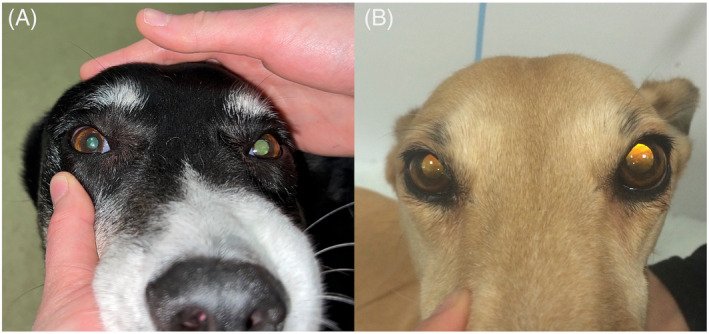

◆◇ 症例(A):雑種犬(10歳オス)◇◆

●主訴:急性発症の運動失調、その直前に嘔吐

● 神経所見:

・左散瞳、左のPLR(対光反射)不完全

・右捻転傾斜、左急速相の回転性眼振

・左前後肢の姿勢反応低下

◆◇ 症例(B):グレイハウンド(8歳メス)◇◆

●主訴:急性の起立不能、左前後肢の負重低下

●神経所見:

・左散瞳、PLR正常

・左の瞬目反応消失(視覚は正常)

・右捻転傾斜、右腹側斜視

・左前後肢の姿勢反応低下

症例はいずれも前庭症状(逆向性)とともに、一過性の片側性散瞳